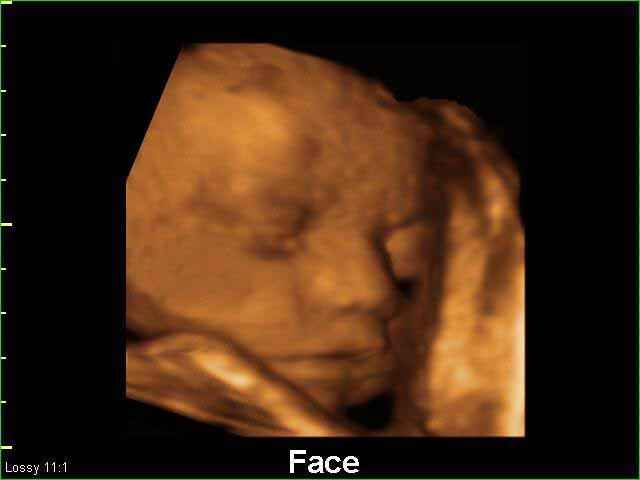

- صور لوجه الجنين في داخل الرحم

- صور جانبية لرأس الجنين

صور لوجه الجنين بجهاز الالتراساوند ثلاثي الأبعاد | الدكتور نجيب ليوس

- أهمية التصوير بالموجات فوق الصوتية رباعي الابعاد في الحمل 4D ultrasound